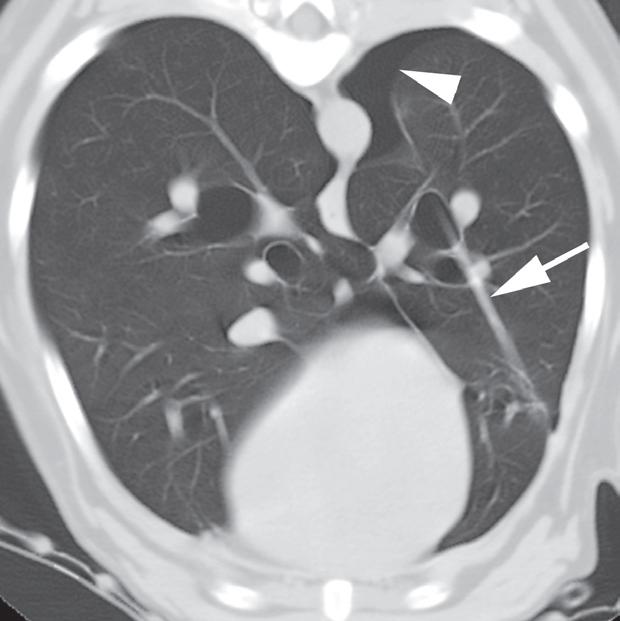

Rycina 4.6.3. Pęcherze płucne (pies) TK

Badanie wykonano u 13-letniego foksteriera z pojedynczym gruczolakorakiem płuc (nie ukazano na rycinie).

Reprezentatywne obrazy TK środkowej i doogonowej części klatki piersiowej, uporządkowane od strony doczaszkowej do doogonowej, ujawniły liczne cienkościenne pęcherze o różnej wielkości. Pęcherze były kuliste i odróżniały się od rurowatego kształtu dróg oddechowych podczas oglądania kolejnych obrazów. Miały również większą średnicę, niż można by oczekiwać w przypadku dróg oddechowych na obwodzie płuca (a–c – duże strzałki). W przeciwieństwie do pęcherzy, drogi oddechowe się rozgałęziały (c – grot strzałki) i towarzyszyły im tętnice oraz żyły płucne (b, c – małe strzałki). U tego pacjenta pęcherze nie powodowały żadnych objawów klinicznych i uznano je za rozwojowe. Ocena makroskopowa i mikroskopowa zmian z usuniętego podczas lobektomii płuca potwierdziła rozpoznanie obrazowe